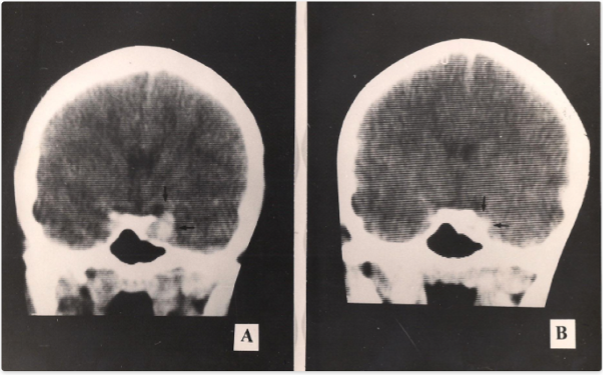

Figure 1. A 34-year-old patient with amenorrhea and hyperprolactinemia (PRL 1630 ng/ml) had a sella CT imaging depicting a pituitary mass on the left (A). Bromocriptine was introduced and after 30 days on 7.5 mg a day, PRL dropped to 32 ng/mL with menses restoration. A repeat CT demonstrated a decrease in tumor size (B).